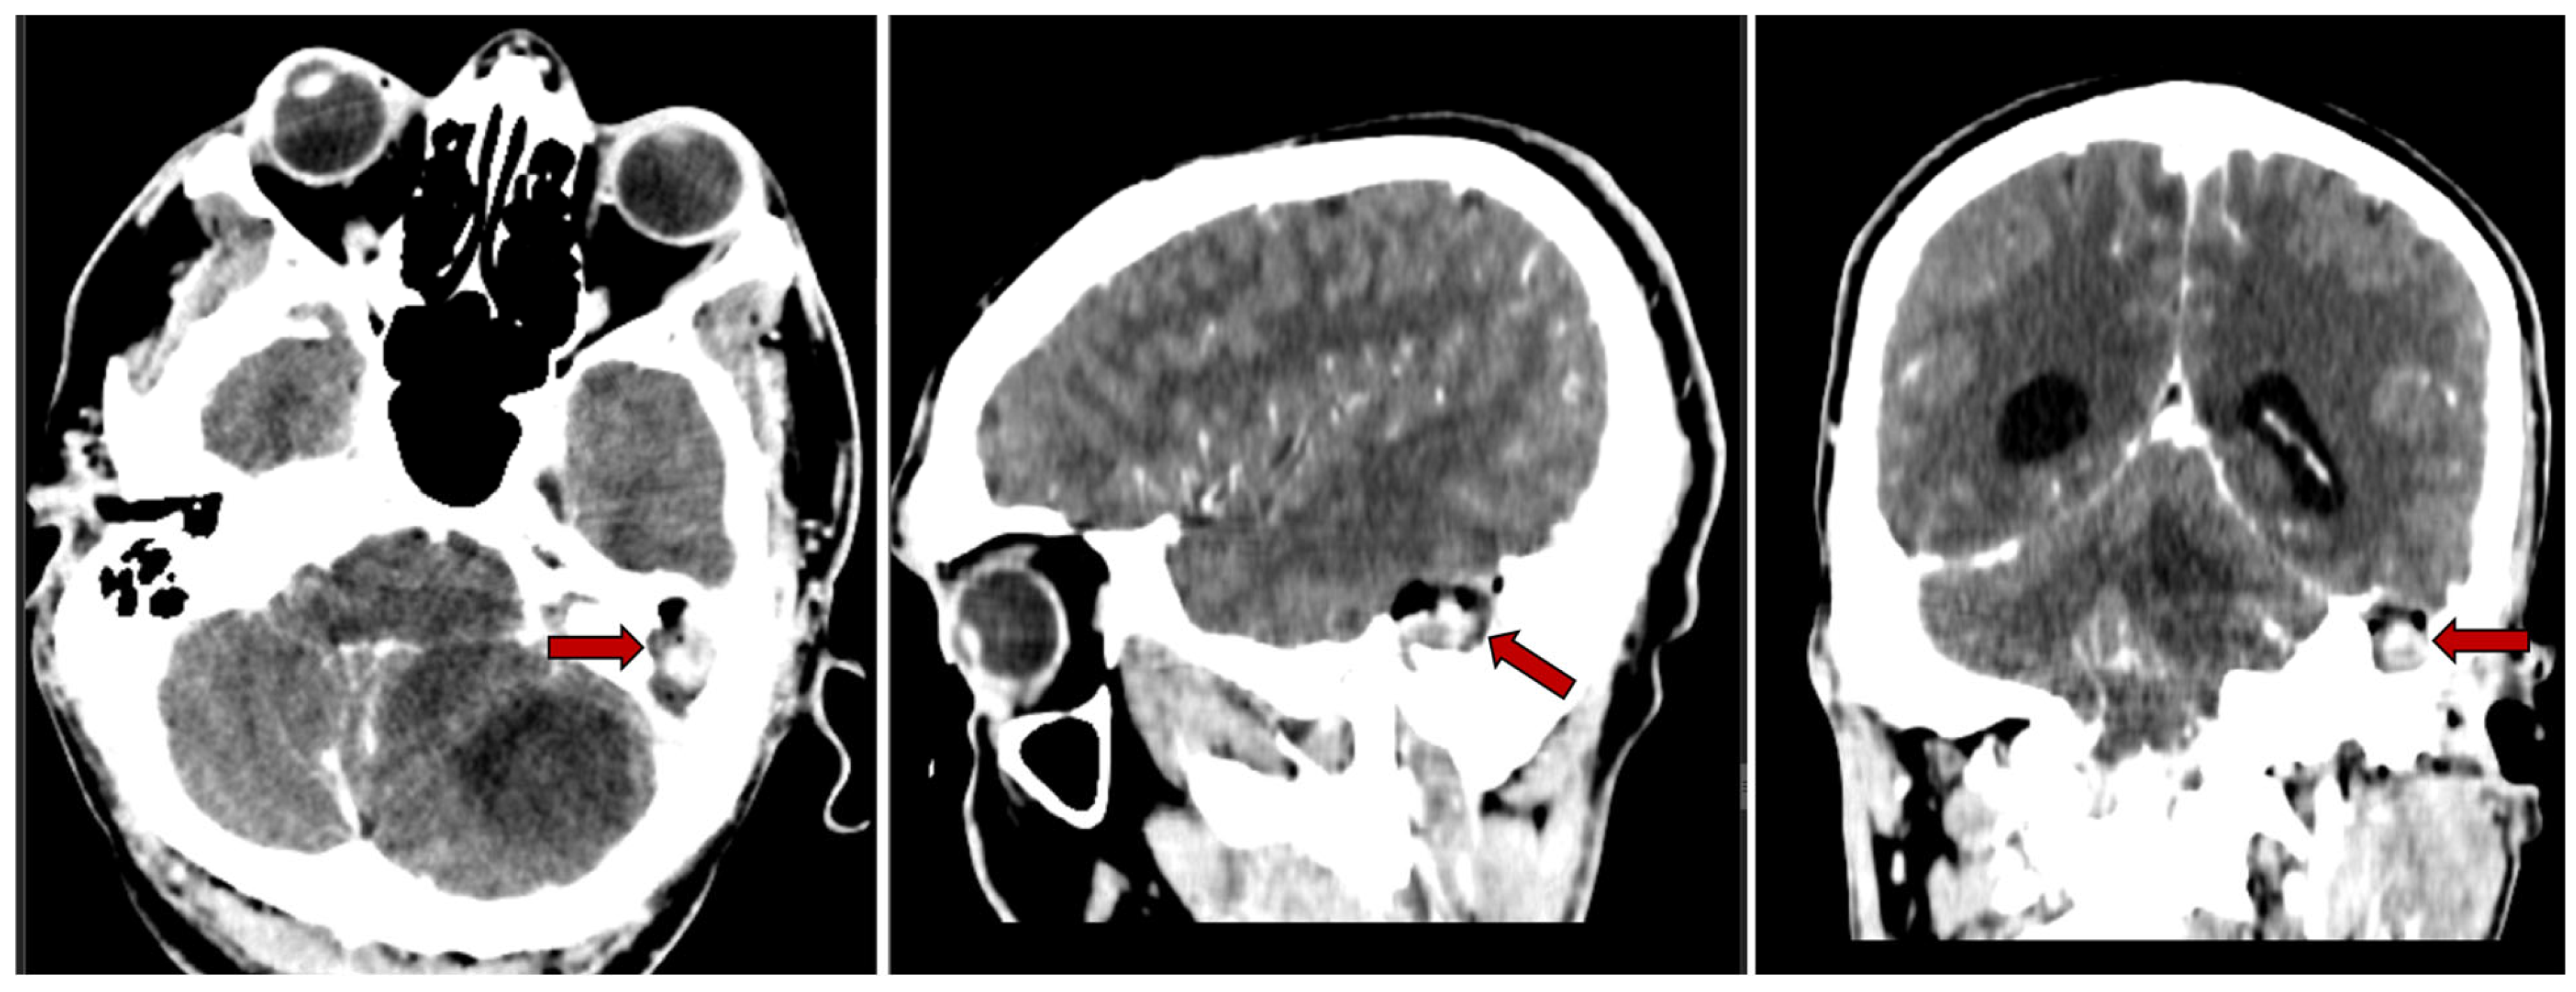

2.2.2. Imaging Studies

3.5. Imaging Studies